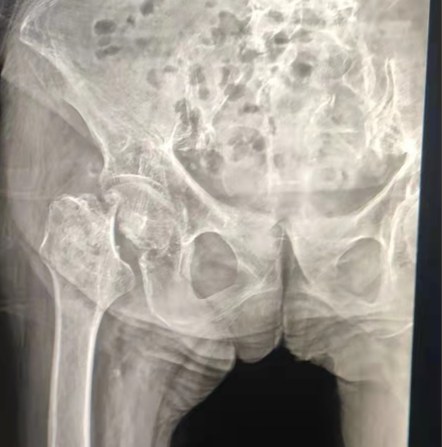

Case Sharing | 70-letni pacjent otrzymał całkowitą wymianę stawu biodrowego z cementowanym układem biodrowym Lepu

Scementowany system biodrowy:

Materiały ze stopu Co-Cr-Mo

Wysoka odporność na zużycie

Wielka wytrzymałość mechaniczna